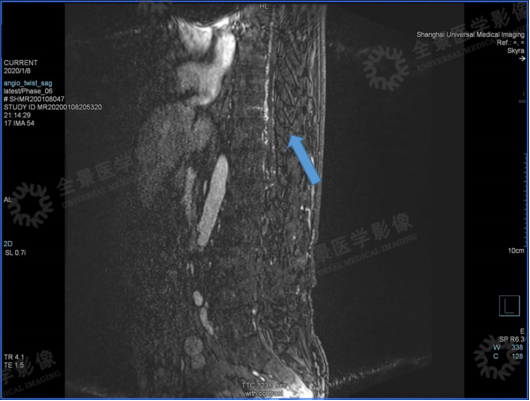

案例二

男,58 岁。右下肢乏力逐渐加重 1 年,双下肢无力 1 月。

2020 年 1 月 8 日,肌电图示:腰骶段脊髓神经损害。

DSA 结果:硬脊膜动静脉瘘。